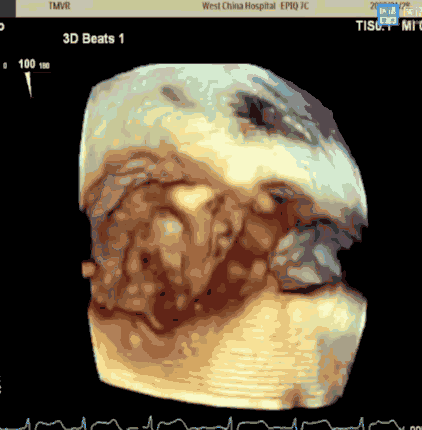

术前经食道超声评估

该例患者为66岁老年女性,体格瘦小、虚弱,因劳力性呼吸困难等心力衰竭症状就诊,既往有持续性房颤病史,经充分优化药物治疗后仍有相关症状。超声心动图提示重度二尖瓣返流(MR 4+),有效返流口面积为0.51cm²,返流量67mL,瓣口面积为4.8cm²;轻度三尖瓣返流;LVEDD 60mm,LVESD 52mm,LVEF 37%。诊断考虑为扩张型心肌病、功能性重度二尖瓣返流(Carpentier IIIb型)、心房颤动、心力衰竭(HFrEF)。多学科团队讨论后认为其有二尖瓣干预指征,外科手术风险高危,决定使用Peijia HighLife TSMVR系统行经股静脉房间隔二尖瓣置换术。